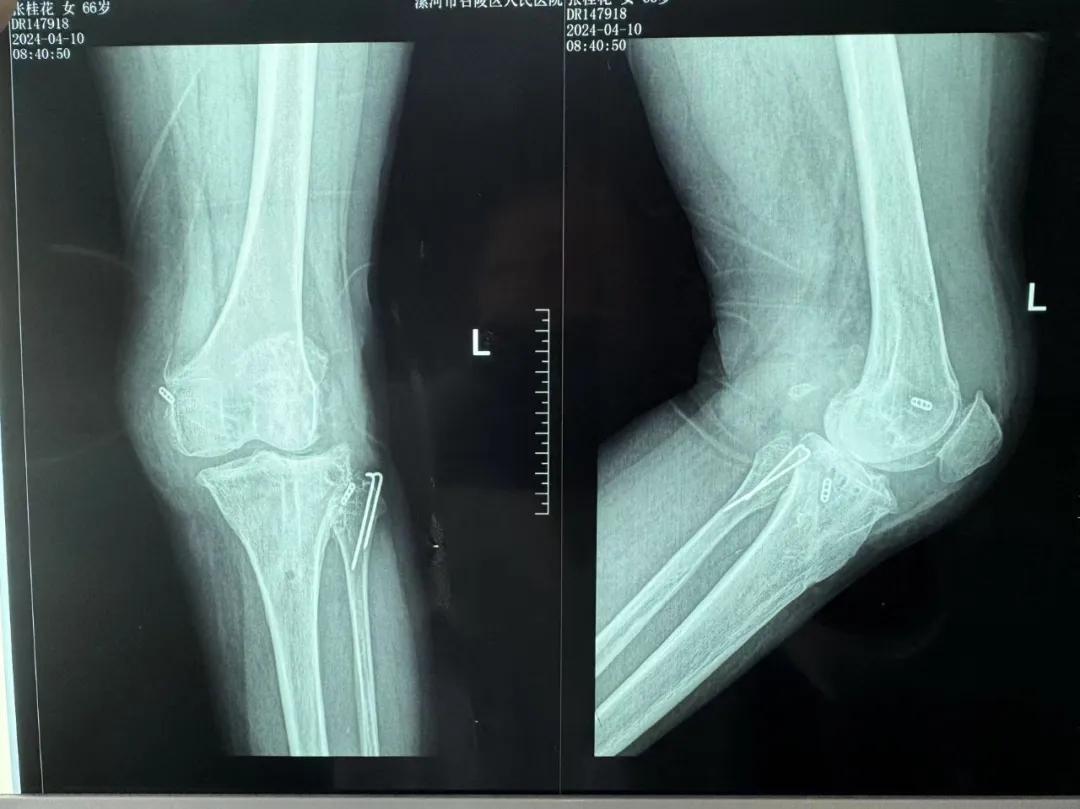

患者來院后,漯河市骨科醫(yī)院(漯河醫(yī)專二附院、漯河市立醫(yī)院)主治醫(yī)師康樂便成了她的管床醫(yī)生。在經(jīng)過詳細(xì)的術(shù)前診斷與檢查后,關(guān)節(jié)外科主任李付彬組織科室團(tuán)隊(duì)針對患者的診斷情況進(jìn)行術(shù)前討論——患者為重度膝關(guān)節(jié)骨關(guān)節(jié)炎,需進(jìn)行人工關(guān)節(jié)置換。但術(shù)前的評估結(jié)果顯示:患者膝關(guān)節(jié)側(cè)方不穩(wěn)定,單純行初次表面膝關(guān)節(jié)置換,術(shù)后仍會存在側(cè)方不穩(wěn)的情況,會影響術(shù)后效果以及假體使用年限,不僅無法完全恢復(fù)膝關(guān)節(jié)功能,還會加重患者的經(jīng)濟(jì)負(fù)擔(dān)。

為了盡可能給患者帶來更好的治療效果,減輕其經(jīng)濟(jì)負(fù)擔(dān),經(jīng)綜合評估后,李付彬主任帶領(lǐng)團(tuán)隊(duì)制定了最終的手術(shù)方案——決定使用髁限制性膝關(guān)節(jié)假體(LCCK)置換膝關(guān)節(jié)。作為解決患者病痛的最優(yōu)方案,這項(xiàng)手術(shù)具體實(shí)施的難度并不小,需要在術(shù)中根據(jù)截骨情況進(jìn)行多次評估和實(shí)時調(diào)整,這就要求主刀醫(yī)生不僅要具備過硬的專業(yè)技術(shù)與能力,還要能夠結(jié)合自身的經(jīng)驗(yàn)準(zhǔn)確判斷、精準(zhǔn)操作。

手術(shù)過程中,關(guān)節(jié)外科團(tuán)隊(duì)為患者進(jìn)行了標(biāo)準(zhǔn)截骨,經(jīng)過評估,患者膝關(guān)節(jié)仍存在膝關(guān)節(jié)側(cè)方不穩(wěn)定,便按照原定手術(shù)計(jì)劃使用LCCK假體進(jìn)行了膝關(guān)節(jié)置換。經(jīng)過再次評估,患者膝關(guān)節(jié)穩(wěn)定性恢復(fù),下肢力線正常,這臺高難度的LCCK膝關(guān)節(jié)置換手術(shù)在一小時內(nèi)便順利完成!術(shù)后第二天,患者就能夠自主下床負(fù)重活動,功能恢復(fù)良好。